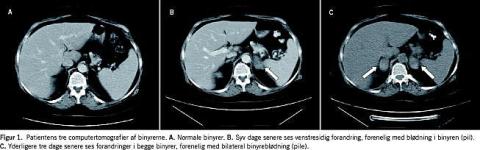

En 57-årig kvinde, der havde SLE og sekundært APS, blev indlagt på kirurgisk afdeling med diagnosen abdominalia. Patienten havde forud for indlæggelsen haft diffuse mave-smerter i tre uger med temperaturforhøjelse og kvalme. Ved indlæggelsen havde hun smerter i venstre fossa iliaca, et blodtryk på 141/93 mmHg og en temperatur på 37,7 °C. Patientens tilstand blev opfattet som forårsaget af en diverticulitis og antibiotisk behandling med metronidazol, gentamicin og penicillin blev iværksat. Patienten blev undersøgt med CT (Figur 1 ), men man fandt normale forhold, herunder også normale binyrer. Efter en initial bedring, forværredes almentilstanden på ottendedagen, og en ny CT dagen efter viste en affektion af venstre binyre, som i første omgang tolkedes som en absces. På tiendedagen fik patienten hypotension, og en tredje CT blev foretaget. Den viste let isodense områder i begge binyrer, hvilket tyder på blødninger. På dette tidspunkt havde patienten et blodtryk på 88/59 mmHg og blev tiltagende træt, mat og konfus.